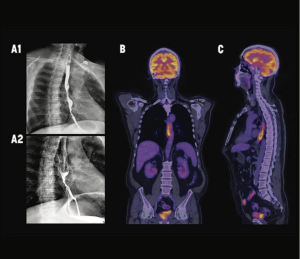

A rare occurrence, cancer in the esophagus requires an individualized treatment plan.